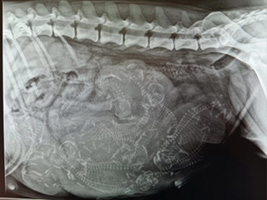

√ Diagnosi e monitoraggio ecografico e radiografico della gravidanza